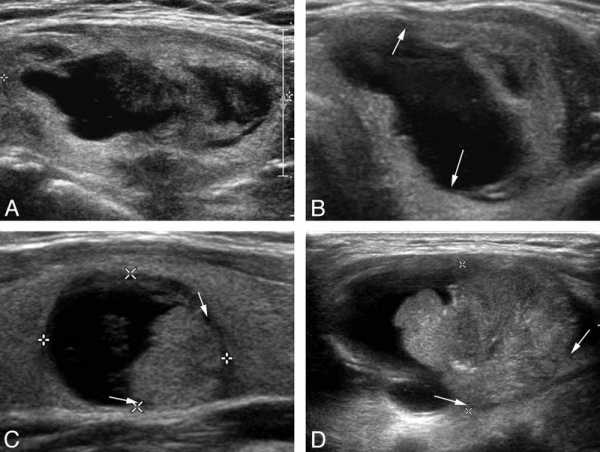

- Очаги изменений – участки, характеризующиеся снижением (гипоэхогенность), отсутствием (анэхогенность) или повышением (гиперэхогенность) акустического ответа ультразвука. Таких образований в норме быть не должно, хотя допускается наличие небольших, до 4 мм, анэхогенных участков – единичных увеличенных фолликулов железистой ткани. Патологические же очаги, выявленные в структуре ткани, представляют собой узлы щитовидной железы. Узлы могут быть единичными и множественными. Единичные узлы малых размеров (1–3 мм) обычно не подлежат лечению и часто исчезают со временем самостоятельно. Образования более 3 мм, как правило, требуют уточнения диагноза.

О чем же свидетельствуют отклонения нормальных размеров органа от нормы в ту или иную сторону? У здоровых структура тканей однородная, средней эхогенности. Образования в ткани не должны превышать 2мм в диаметре. Эти элементы называются фолликулами и обладают способностью, как появляться, так и самостоятельно рассасываться. Если образование больше 1см – это узел, требующий дальнейшего исследования.

Нужно отметить также иные отклонения от нормы, которые могут встречаться в щитовидке. На УЗИ оцениваются однородность структуры тканей органа и их эхогенность. В нормальной ткани железы могут встречаться образования:

- узлы — увеличенные коллоидные фолликулы, которые подлежат дополнительному исследованию в случае их роста больше 1см. Образования могут быть единичными и множественными. Если образование имеет доброкачественную природу, растет медленно, функционированию органа не мешает, то лечения оно не требует;

- кисты — полости с капсулой и с коллоидным содержимым, четко очерченные. Растут медленно;

- опухолевые образования четко отграниченные от здоровой ткани — они могут оказаться как доброкачественными аденомами, так и злокачественными карциномами. Как правило, они подлежат удалению;

- злокачественные узлы при некоторых видах рака (папиллярном, медуллярном, анапластическом) хорошо идентифицируются на УЗИ благодаря нечеткой размытой форме. Структура смотрится как неоднородная, просматриваются некротизированные участки, области скопления жидкости. Образования быстро растут и могут метастазировать в окружающие лимфоузлы.

Когда изучаются в щитовидной железе узлы размеры в соответствии с нормой ,оценивается также их эхогенность. Узлы различаются на:

- изоэхогенные с четким контуром и с малоизмененной структурой ткани. Параметры щитовидки при этом сохраняются неизмененными;

- гиперэхогенные сопровождаются изменением структуры тканей. Часто такие новообразования возникают при формировании злокачественных опухолей;

- гипоэхогенные узлы образуются при отмирании фолликулов, при этом отмечается диффузное изменение тканей;

- анэхогенные новообразования имеют кистозную оболочку, а внутри заполнены жидкостью.